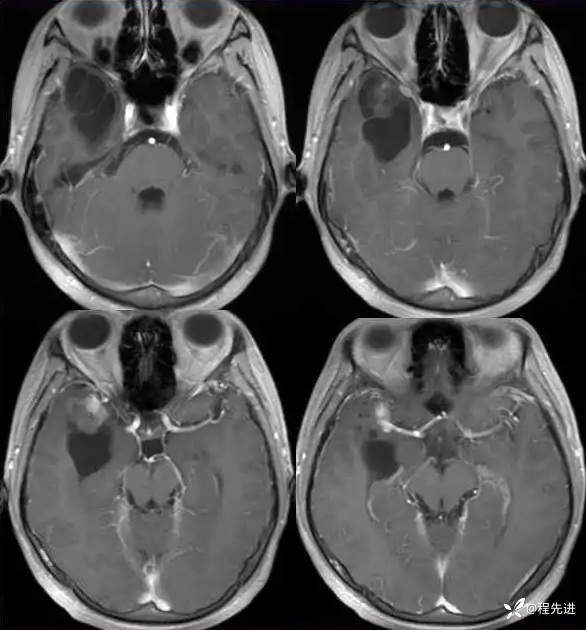

现病史:患者10天前无明显诱因突发四肢抽搐伴意识障碍,发作时口吐白沫,牙关紧闭,大约5分钟后患者清醒,醒后不能回忆发作时情况,查头颅MRI检查提示右侧颞叶占位。门诊拟“继发性癫痫”收住入院。患者病程中无明显头痛头晕,食纳睡眠可,大小便可,体重无明显变化。

T1:

T1增强: